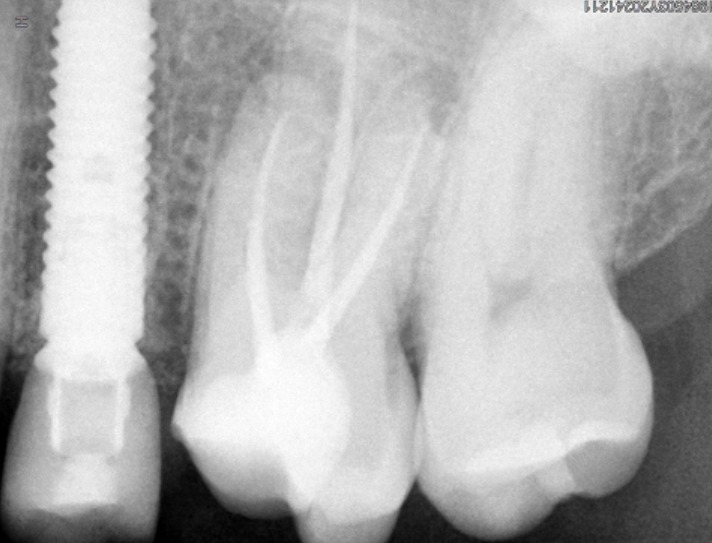

- Radiografía digital para evaluar el caso y controlar cada etapa del tratamiento